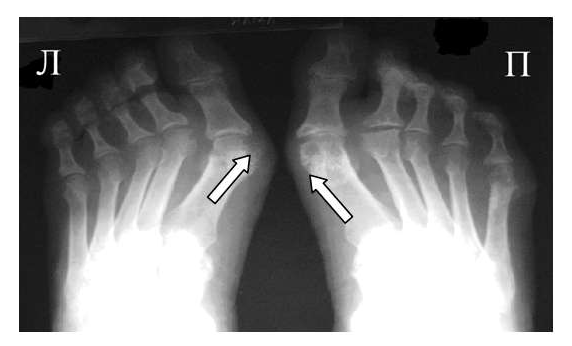

Для подагрического артрита характерно преимущественное поражение дистальных отделов стоп с преобладанием изменений в области I плюсне-фаланговых сочленений, реже изменения выявляются в мелких суставах кистей. При остром подагрическом артрите рентгенологические изменения, как правило, отсутствуют. Поэтому речь идет об изменениях, характеризующих хроническую стадию болезни. Типичным для хронического подагрического артрита является обнаружение узловых образований (тофусов) в костях в виде кистовидных просветлений и участков повышения плотности мягких тканей в области фаланг пальцев кистей и стоп. Деструкция костной ткани в виде эрозий, часто выявляемая при хроническом течении подагры, локализуется в основном на краях эпифизов костей и в дальнейшем распространяется на центральные отделы суставов.

Эрозии при подагрическом артрите имеют округлую или овальную форму, часто со склеротическим ободком. Склеротический ободок вокруг внутрисуставного тофуса создает типичный для подагрического артрита симптом «пробойника» (см. рис. 1).

В отличие от ревматоидного артрита и полиостеоартроза ширина суставной щели при подагре обычно сохраняется в норме даже в поздних стадиях заболевания. Также для хронической стадии, в отличие от ревматоидного артрита, не характерен остеопороз. Таким образом, I плюснефаланговый сустав наиболее характерная локализация при подагрическом артрите.

Рис. 2 Симптом «пробойника» в головках плюсневых костей обеих стоп в сочетании с вальгусной девиацией I плюсне-фаланговых суставов

Эрозии часто обнаруживаются в верхней и медиальной части плюсневой головки и часто в сочетании с вальгусной девиацией суставов. Типичным является асимметричность изменений (рис. 2).